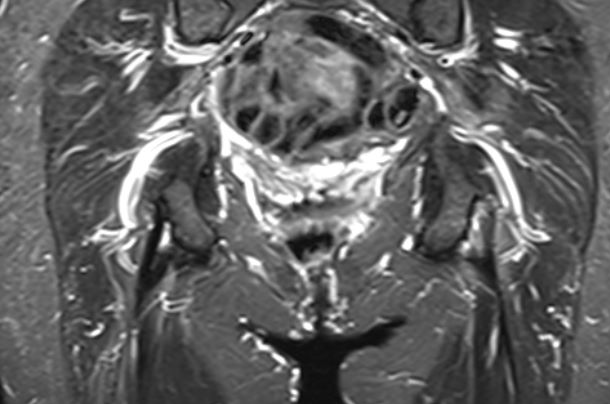

MRI

Peritendinous edema / low grade partial tears / tendinopathy

High grade partial tears